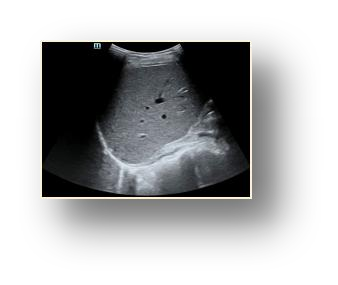

Most deep neural networks (DNNs) based ultrasound (US) medical image analysis models use pretrained backbones (e.g., ImageNet) for better model generalization. However, the domain gap between natural and medical images causes an inevitable performance bottleneck. To alleviate this problem, an US dataset named US-4 is constructed for direct pretraining on the same domain. It contains over 23,000 images from four US video sub-datasets. To learn robust features from US-4, we propose an US semi-supervised contrastive learning method, named USCL, for pretraining. In order to avoid high similarities between negative pairs as well as mine abundant visual features from limited US videos, USCL adopts a sample pair generation method to enrich the feature involved in a single step of contrastive optimization. Extensive experiments on several downstream tasks show the superiority of USCL pretraining against ImageNet pretraining and other state-of-the-art (SOTA) pretraining approaches. In particular, USCL pretrained backbone achieves fine-tuning accuracy of over 94% on POCUS dataset, which is 10% higher than 84% of the ImageNet pretrained model. The source codes of this work are available at https://github.com/983632847/USCL.